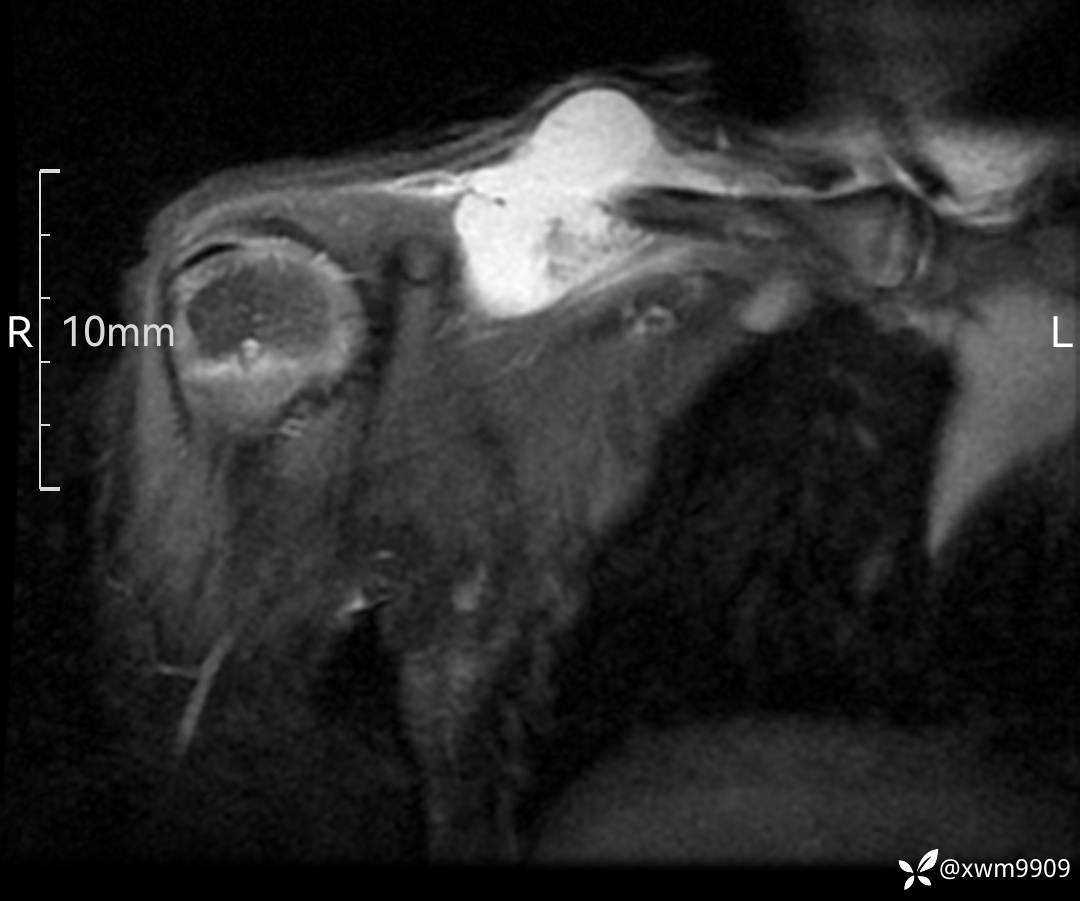

3、查体,右锁下方可及一约5x6Cm肿物,软丶边清丶未见明显发红,肤温不高,压痛明显,不可推动,稍有波动感。其他无特殊。

2、CT、MR肿块内可见液-液平面,常见有哪些疾病。